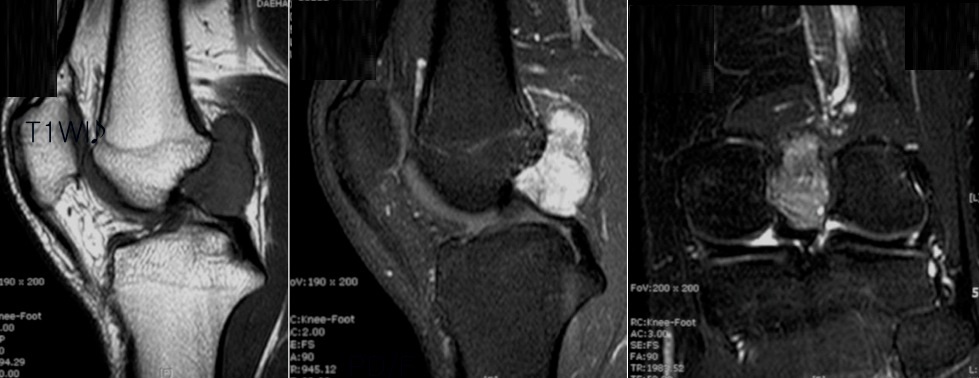

Figure 1 for case pigmented villonodular synovitis ( RID3641 )

Figure 1

Figure 2 for case pigmented villonodular synovitis ( RID3641 )

Figure 2

Figure 3 for case pigmented villonodular synovitis ( RID3641 )

Figure 3